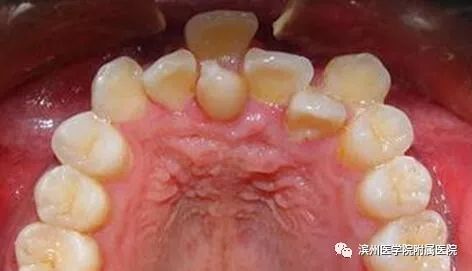

李奶奶的宝贝孙子6岁半了,上颌前面的两颗门牙已经替换了三个多月,可是两颗新牙间缝隙不见变小,反而越来越大了,远没有乳牙长得那么整齐。孙子门牙有大缝这事最近让李奶奶一直着急上火,平日总挂在脸上的笑容也不见了,今天一大早就带着孩子到滨州医学院附属医院儿童口腔科检查。儿童口腔科的医生经过专科查体并配合X线检查,发现是孩子的两颗新长门牙之间有一颗多生牙在作怪。

说说我的外形吧!普通牙齿都是左右对称的双胞胎,一点个性都没有,而我想长成什么样就长成什么样,大部分时候我都是酷酷的小火箭造型。有些时候,我会“装扮”成普通牙齿的模样混在它们中间,哈哈,让大家分不清哪个是我。

看完这些,大家对多生牙有所了解了吧,正如上面所讲,如果是在替牙期,多生牙的位置会阻碍正常新牙的萌出通道,导致对应恒牙的萌出位置发生异常,例如牙齿发生扭转、倾斜、拥挤或牙缝过大甚至不能萌出。而且,多生牙奇怪的外形也会严重影响小主人口腔美观及心理健康;也有可能导致含牙囊肿的发生,若无视它继续生长,骨质逐渐向周围膨胀,则会形成面部畸形。